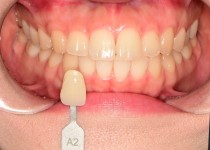

스탠다드 미백(오스템 뷰티스)

스탠다드 미백 (오스템 뷰티스)